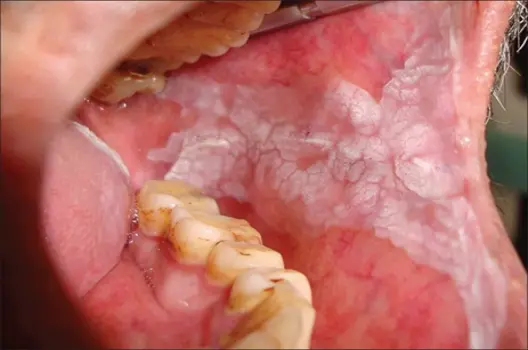

Invivo evaluation on OSMF

Oral Cancer is a progressive, irreversible condition with a high risk of mortality. The lack of curative options results in severe patient distress.

Existing treatments like corticosteroids, antioxidants, and surgical interventions fail to address the underlying cellular damage or cancer progression.

Most therapies are palliative, not preventive or curative.